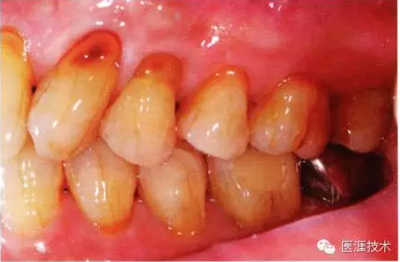

55歲牙周炎男性的臨床照片

55歲男性抽煙患者(1天20支、抽煙35年)。菌斑控制得不好。通過牙周探診,全頜有4~9mm的牙周袋,有1~3度的根分叉部病變。通過X光片觀察,上頜前牙中度牙槽骨吸收,其他地方有中度牙槽骨吸收。受吸煙影響,牙齦纖維性肥厚,呈紅黑色。牙齦幾乎沒有浮腫和發(fā)紅,所以這個病例是從外觀上無法預(yù)測病癥嚴(yán)重程度的病例。